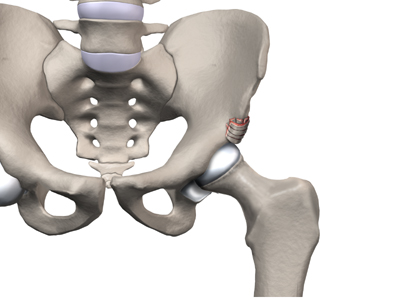

Whatever the true cause of ischemia (lack of blood to the area), the result is bone death (called necrosis) of the femoral head. Without a normal blood supply, the bone loses its strength and shape. The loss of bone density and softening of the head result in a femoral head that is misshaped. With the hip supporting the weight of the body, tiny microfractures in the soft, necrotic bone fail to heal. This is another reason why normal wear and tear results in a deformity.

The main problem with Perthes disease is that it changes the structure of the hip joint. How much it affects the way the hip joint works depends on how much the hip joint is deformed. Muscle weakness and atrophy affecting the thigh and calf muscles may develop over time. The affected leg can shorten as a result of the changes in the hip. The result may be a significant leg length difference. Problems later in life are more likely the greater the deformity after the condition has healed.

In general, the most common problem later in life is the development of arthritis in the hip joint. The type of arthritis that develops in the hip is osteoarthritis (also known as wear and tear arthritis). Just like a machine that is out of balance, the hip joint wears out and becomes painful.